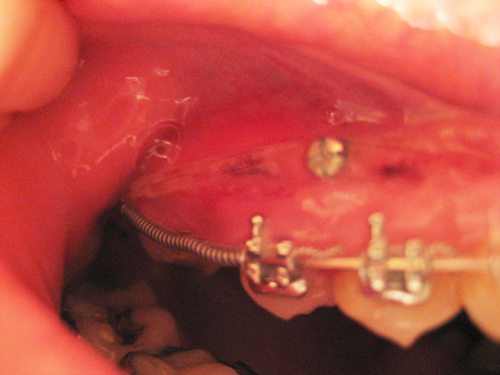

힘이 얼마나 센지 파워체인이 저렇게 잇몸을 눌렀어요..ㅠㅠ

눌렷다기보다 거의 잇몸에 박혔다는 표현이..

어제 치과다녀왔더니 아래사진처럼 스크류 아래로 다시 걸어주셨어요.

상처보이시죠 ㅠㅠ 저게 사진엔 조금 흐리게 나왓어도 폭 파였답니다.

근데 아직도 한쪽면이 저렇게 상처와 닿아있어서 걱정이네요..

스크류 첨 하면 주변 잇몸이 붓는데요, 파워체인이 부은 잇몸을 누른답니다.

보니까 스크류에 파워체인고무줄걸고 철사위엔 스프링걸었나보네요. 전 너무 안아파서 당기기하고있기나 한건지 의심까지 가는 중인데.. ㅠㅠ